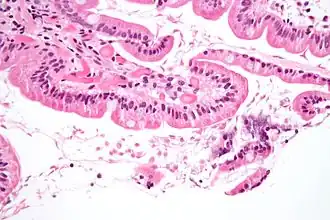

La maladie est due à l’infestation par des protozoaires flagellés : Giardia intestinalis. Les parasites vivent dans l’intestin grêle, à la surface des villosités intestinales. Lors de leur passage dans le côlon, ils se transforment en forme kystique, très résistantes, et sont passivement éliminés avec les selles. Les kystes survivent dans la nature, et vont contaminer un nouvel hôte par ingestion de nourriture ou d’eau contaminée, ou par portage à la bouche de mains souillées. La lambliase est étroitement liée au péril fécal, sa prévalence est corrélée au degré d’hygiène collective et individuelle, au traitement des eaux usées, etc.

Le cycle parasitaire commence par un kyste non infestant éliminé dans les selles d’un individu infecté. Une fois dans l’environnement extérieur, le kyste devient infestant. Un caractère distinctif du kyste est qu’il possède 4 noyaux et un cytoplasme rétracté. Une fois ingéré par l’hôte, le trophozoïte arrive à un stade actif et il est capable de se mouvoir pour trouver sa nourriture. Il se nourrit aux dépens de la muqueuse à l’intérieur du tractus digestif et provoque chez l’hôte des douleurs épigastriques, une distension gazeuse excessive, une diarrhée graisseuse avec du mucus mais pas de sang. Ces symptômes peuvent durer 2 à 4 semaines mais pour un individu intolérant au lactose, les troubles peuvent persister jusqu’à six mois. Après l’étape de prolifération, le trophozoïte subit la phase de reproduction asexuée par scissiparité. Les trophozoites et les kystes résultants de la division traversent alors le système digestif et sont éliminés dans les selles. Les caractères distinctifs des trophozoïtes sont de grands caryosomes et le manque de chromatine périphérique, donnant aux deux noyaux l’aspect d’un halo. C’est une forme primitive de protozoaires à laquelle font également défaut les mitochondries.

Les enfants sont exposés au risque de destruction des villosités digestives, ce qui entraîne un syndrome de malabsorption digestive.